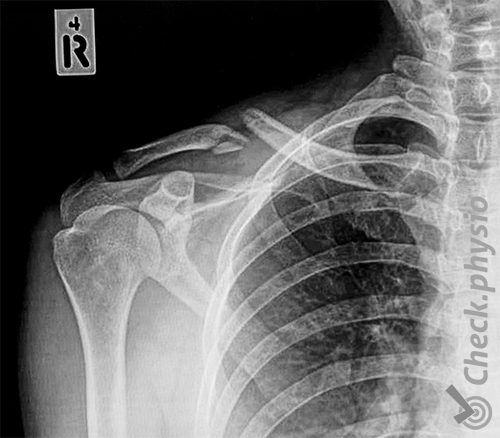

A collarbone fracture is not difficult to diagnose due to the location of the collarbone near the surface, making it easy to see and feel. An X-ray is usually done to get an indication of the fracture and the position of the collarbone. This gives insight into the healing process and can help rule out problems with underlying tissues such as nerves and blood vessels.